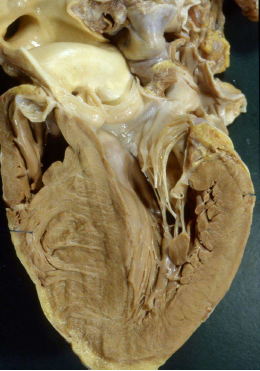

Cardiomiopatia

dilatativa

(DCM):

ipertrofica

(HCM):

Ipertrofia

asimmetrica, setto

subaortico